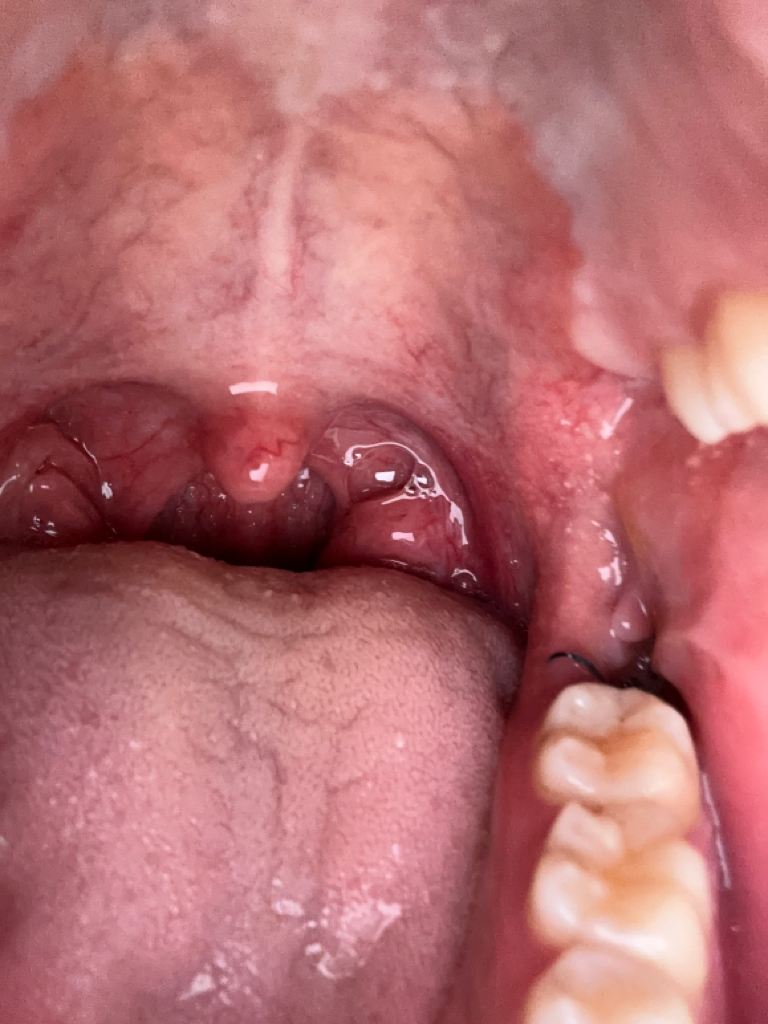

사랑니 발치후 잘 아물고있는지 봐주실 수 있을까요? (사진있어요)

사랑니 발치후 3일차입니다 통증은 없어요. 피도 안나구요. 양치를 최대한 살살하고있는중인데요 아직 실밥은 풀지않아서 이물감은 좀 있네요. 염증소견이 보인다거나 하진 않는지 잘 아물고있는지 이 사진으로 판단이 되실까요?ㅠ

사진상으론 아무런 문제가 보이지 않습니다. 실밥 잘 뽑으시고 지금처럼 관리하시면 됩니다.

발치 3일째이면 정상적으로 아물고 있습니다. 건드리면 아프거나 피가 스며 나오기도 하지만 문제되지 않습니다.

사진상으로 보면 잘 아물고 있는거 같습니다. 음식이 남아 잇지 않도록 식후에 물로 헹궈주시는게 좋습니다.

발치부위가 정확히 보이진 않으나 위생관리 상태가 괜찮고 별다른 임상증상도 없으므로 잘 치유되고 있는것으로 보입니다

사진으로만 봤을 경우에는 크게 문제가 없이 잘 아물고 있는 것으로 보입니다.

사랑니를 발치하고 나면 사랑니를 발치한 부위에 혈병이 잘 형성되어 있어야 되기 때문에 해당 부위를 자극하지 않는 것이 좋습니다.

또한 실밥을 풀러 치과에 내원에서 해당 부위에 이물질이 없는지 한 번 더 확인하는 것이 좋습니다.

사진상으로 보았을때 실밥도 느슨하지만 잘 묶여있고

염증도 없고 붓기도 별로 없이 잘 낫고 있네요.

걱정하지 않으셔도 괜찮겠습니다.